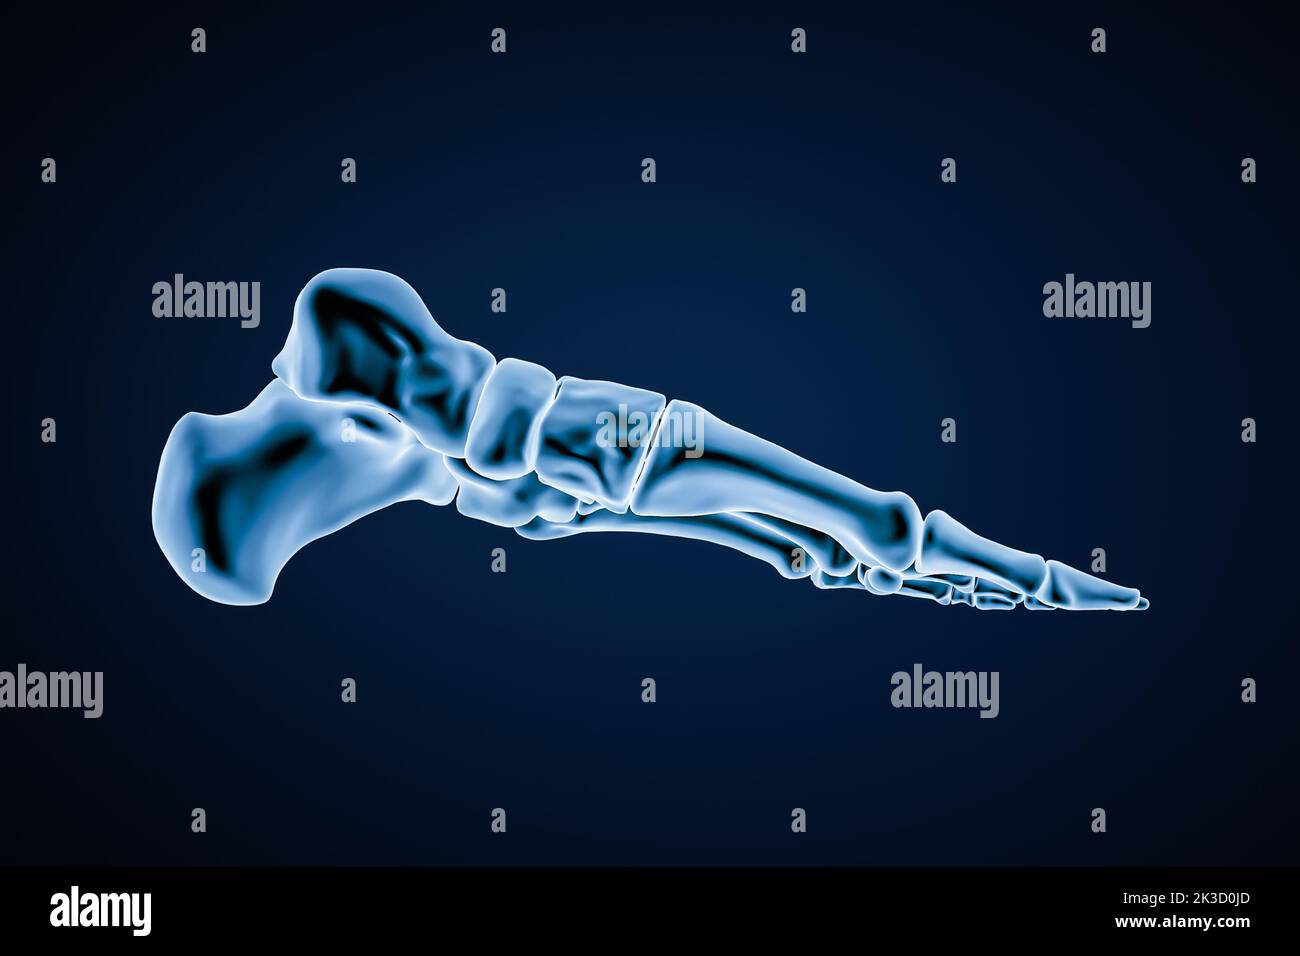

RF2K3D0JR–OS précis des os du pied gauche humain ou squelette 3D illustration du rendu. Vues latérales, médiales, dorsales et plantaires. Anatomie, ostéologie, squelette

RF2K1RE44–Vue latérale ou en profil d'os précis du pied gauche humain avec contours du corps sur fond bleu 3D illustration de rendu. Anatomie, ostéologie, ortho

RF2K3D0JD–Vue intérieure médiane ou profil des os du pied gauche humains précis isolés sur fond bleu 3D illustration de rendu. Anatomie, ostéologie, orthopédiste